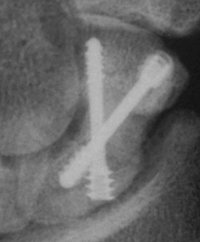

Case 4. Nonunion with a graft and screws placed in both directions from a single palmar approach, hyperextending the wrist for the proximal entry...

Click for larger image

and with the graft:

and with consolidation,